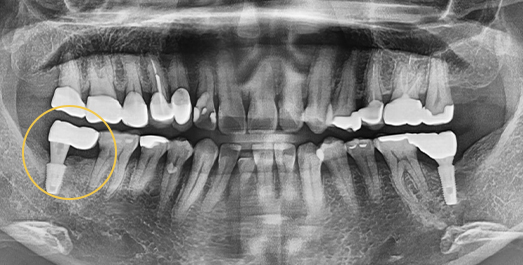

Implant Revision Surgery

Revision implant surgery is more challenging

and complex than the original procedure

Improper implant surgery or inadequate implant maintenance can lead to complications accompanied by pain. Implant revision surgery involves removing the existing implant, rebuilding the alveolar bone, reshaping the gingival contour,

and placing a new implant in the correct position.

• BEFORE: 2021.11.02

• AFTER: 2022.01.19

An implant placed at another clinic was found to be significantly mispositioned,

requiring revision surgery to correct the placement to the proper position.